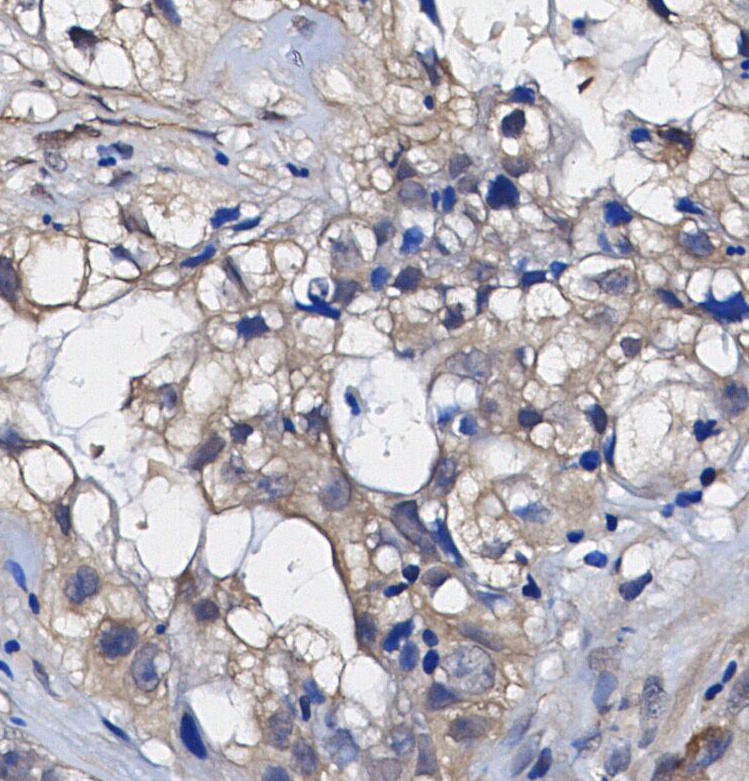

• Immunohistochemical analysis of formalin fixed paraffin embedded human Lung adenocarcinoma tissue with F0592 at 1/100 dilution.

Phospho-Axl (Tyr702) Antibody [F18P21] detects endogenous levels of Axl only when phosphorylated at Tyr702.

AXL is a member of the TAM receptor family, which includes TYRO3, AXL, and MER. Its high-affinity ligand is growth arrest-specific protein 6 (GAS6), and the GAS6/AXL signaling pathway plays a significant role in promoting cancer cell survival, proliferation, migration, invasion, epithelial-mesenchymal transition (EMT), angiogenesis, drug resistance, immune regulation, and stem cell maintenance. AXL consists of extracellular, transmembrane, and intracellular domains. The extracellular region features two immunoglobulin (Ig)-like repeats and two fibronectin type III (Fro III)-like repeats that resemble neural cell adhesion molecules (NCAMs). The Ig motifs mediate AXL’s interaction with GAS6, regulated by the Fro III repeats. The intracellular domain is essential for auto-phosphorylation and kinase activity. GAS6 binding activates downstream signaling pathways, including phosphatidylinositol 3-kinase (PI3K), Akt, S6K, and NF-κB. AXL has six identified phosphorylation sites: Tyr698, Tyr702, Tyr703, Tyr779, Tyr821, and Tyr866, with Tyr702 phosphorylation observed in certain carcinoma cell lines.